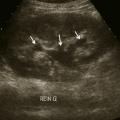

L’échographie abdominale a l’inconvénient d’être opérateur-­dépendante. Ses principales indications sont la lithiase biliaire et ses complications, des douleurs abdominales chez les patients minces et surtout chez la femme pour rechercher une pathologie gynécologique en utilisant le cas échéant des sondes endocavitaires. Ainsi, l’échographie est utile pour affirmer la lithiase biliaire et la cholécystite aiguë (fig. 1) ou objectiver une dilatation de la voie biliaire principale (VBP), rechercher une urétéro-hydronéphrose et des signes indirects en cas de colique néphrétique (fig. 2 et 3), débrouiller le diagnostic des douleurs abdomino-­pelviennes chez la femme.

L’échographie peut montrer une discrète asymétrie des cavités excrétrices rénales, voire l’obstacle lithiasique avec dilatation d’amont (fig. 2 et 3). L’uroscanner complète le bilan et localise si besoin le calcul. Outre le traitement de la cause (calcul, compression extrinsèque…), le traitement antalgique est primordial : anti-inflammatoires non stéroïdiens (AINS), paracétamol, anti­spasmodiques voire dérivés morphiniques. On procédera à la pose d’une sonde urétérale en cas d’anurie (rein unique), de fièvre sur rétention du haut appareil ou de crise hyperalgique.